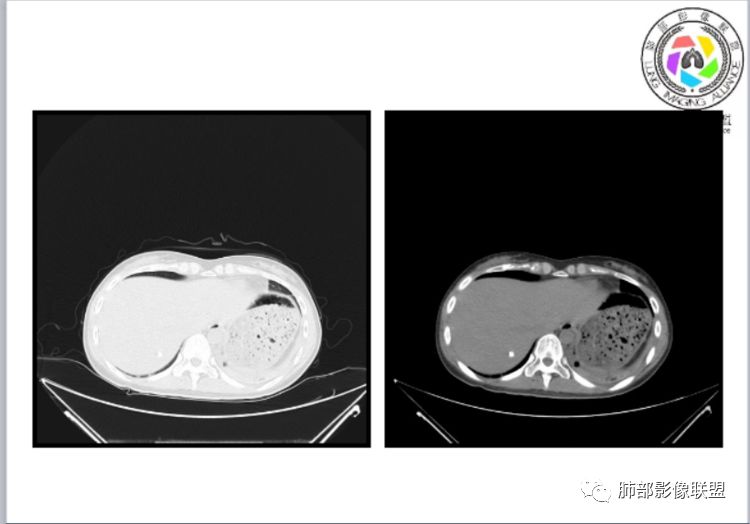

小微:右肺下叶斑片状密度增高影,抗炎治疗6天后复查,双肺下叶出现斑片状密度增高影,排除炎性病变,D2聚体特别高,考虑肺栓塞,肺梗死,建议增强扫描。王开金江津中心医院呼吸科:@岳微-辽宁PLA234医院放射科?支持,患者年轻女性,胸痛主诉,使用雌激素,高危人群,心率快,d二聚体升高,右下叶斑片加肺动脉明显增宽,抗感染无效,要考虑PTE,建议肺动脉ctpa。傅昌瑜:19岁,女性,右侧胸痛2天,发热以中度热为主,D—二聚体升高,肺动脉主干增宽,病灶位于胸膜下,抗感染后增多,近来有服用炔雌醇环丙孕酮片2周期史,诊断:肺栓塞,下一步完善肺CTPA检查。阿仙奴:青年女性,急性起病,胸痛入院,月经不调史,目前服用孕酮片。流感抗体阳性,d二聚体升高,无低氧血症。右肺下叶基底段胸膜下磨玻璃样改变,肺动脉增宽,治疗过程出现发热,复查左下叶胸膜下新发病灶。考虑:肺栓塞(服用孕酮相关)?奔跑的37°Doctor(陆喜红 ) :年轻女性,胸痛 急性病程,有服用雌激素避孕药史(是否有血液循环的改变,高凝状态),实验室D二聚体很高(也是提示血液高凝状态) ,第一次CT,右下肺胸膜下斑片状密度增高模糊影,肺动脉形态密度未见明显异常,抗炎后复查,肺动脉干及其分支,感觉增粗了一点,局部形态有点饱满,双下肺胸膜下片状影增多,锁定肺动脉栓塞应该不会错,建议CTA检查飞鹰行动:青年人,女性,右肺下叶斑片状密度增高影,抗炎治疗6天后复查无好转,,双肺下叶出现斑片磨玻璃影,主肺动脉增粗,结合患者服用的药物和D2聚体特别高,考虑肺栓塞,建议CTA。李:口服避孕药,有危险因素,肺动脉较主动脉增宽,D二聚体增高,胸膜下片状影,考虑肺栓塞;@晨义工张帅,医附属潞河医院呼吸?是否痰中带血很关键,不知有没有张帅:患者入院后第七天出现痰中带血风之子:病程中有发热,D—二聚体升高,肺动脉主干增宽,病灶分布于胸膜下,抗感染后增多,结合服药史诊断:肺栓塞,建议CTPA检查。不支持的地方是没有低氧血症,不明白为什么第二次复查ct双侧乳腺不对称,按理乳腺炎多见于哺乳期张帅:大家方向都在考虑肺栓塞:我提问两个问题:1 周围毛玻璃怎么回事?2左下肺小叶间隔增宽怎么回事?笨丫头:周围的磨玻璃应该考虑是肺梗死后出血渗出,同时合并机化性炎症小叶间隔增宽,我考虑应该是梗死后炎性渗出wonderful:我不支持肺栓塞 不能解释发热原因

水晶石头:患者青少年女性,右侧胸痛2天就诊。有咳嗽,无痰。初次胸部CT:右下肺片状模糊影。入院后经头孢美唑、莫西沙星抗感染治疗6天后复查胸部CT:右下肺病灶加重,且左下肺出现类似病灶。结合其气管镜气道无异常,病程中有发热,D—二聚体升高,近来因月经不调有服用炔雌醇环丙孕酮片史。诊断考虑良性非感染性。肺栓塞可能性大,鉴别血管炎及子宫内膜肺异位可能。流心明智:女性,19岁,右侧胸痛2天,中度热为主,D—二聚体升高,影像:肺动脉主干小于29mm,病灶位于右下肺胸膜下,斑片影,胸膜侧宽基底,抗感染后增多,左下肺亦出現类似病灶,似有反晕、融冰征。近来有服用炔雌醇环丙孕酮片2周病史,考虑诊断:肺栓塞。具体性质及发病机制有待进一步检查。尘缘:@吴永丽 灌云县医院 呼吸?应该是的,左下肺的磨玻璃影像后面也支持有出血改变所以可能就是一个子宫内膜异位出血合并感染

没意见:同意各位老师高见,临床D二聚体比这个高的多了,这个指标只能作为筛选条件,就这个病例来说,指向性还是比较明显的,没看出还有别的可能wonderful:d2聚体阴性有排除意义 阳性与数值意义不大天涯:感染有,是不是和栓塞有关?还要CTA,子宫内膜异位思路很好不倾城不可爱:会不会子宫内膜异位症呢采莲:青年女性,有口服避孕药病史,双下肺胸膜下多发斑片磨玻璃影,有融冰征,二聚体高,还是首选肺栓塞可能性大。至于子宫内膜异位症见得少。崇军:第一次点晕征,六天以后加重,而且左下肺病灶明显增大,磨玻璃,pct正常,抗感染无效,所以感染性病变排除。肿瘤性病变,太年轻,暂排。血管炎,化验为阴性。少见病子宫内膜移位不会六天以后加重。结合化验指标,还是肺栓塞可能南边:曹老师考虑子宫内膜异位症?有没有考虑肺栓塞的?我们下一步该如何处理?

1、一个或多个胸膜下斑片高密度影(梗死、出血、肺不张、肺水肿、炎性渗出),典型为胸膜下楔形影 ,尖端指向肺门

5、膈肌升高、胸腔积液、心包积液

3.影像:病变胸膜下多发斑片影,提示与血管有关,早期病变为渗出,应该是早期的炎性渗出,病灶抗感染治疗后实变区增多、变大,临床症状又出现咯血,CT上应该合并了肺泡出血、梗死、肺不张及肺水肿;